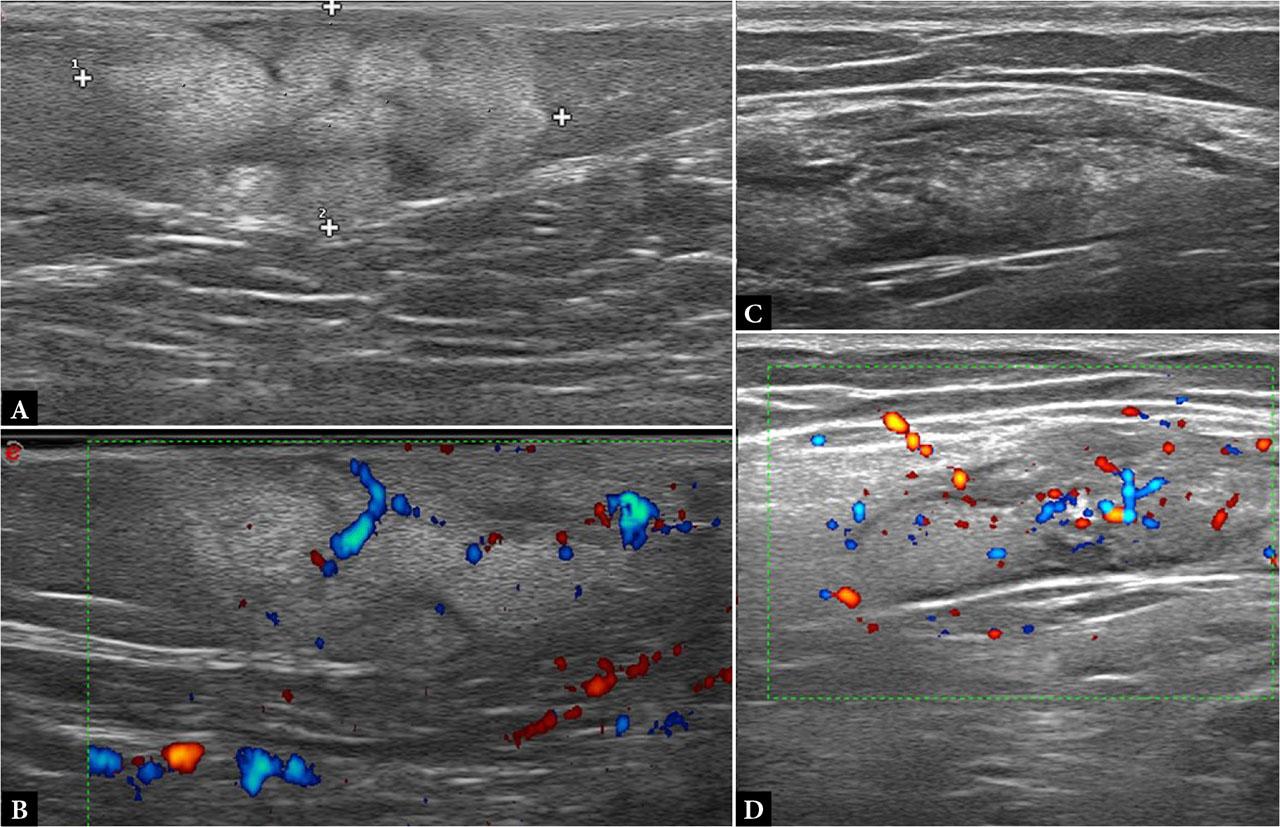

On ultrasound, malignant panniculitis may demonstrate plaque-like areas of cutaneous thickening and mass formation or as ill-defined areas within the subcutaneous fat containing hypoechoic foci on a hyperechoic background, with hypervascularity and a low resistive index on Doppler evaluation(25) (Fig. 7).

Malignant panniculitis: A, B. B-mode and Power Doppler images of a subcutaneous nodule in the posterior aspect of the right arm in a 47-year-old woman with lymphoblastic leukemia, showing a poorly marginated area in the subcutaneous tissue with increased volume and echogenicity, hypoechoic lines, and central and peripheral hyperemia; C, D. B-mode and Power Doppler images of a subcutaneous nodule in the posterior aspect of the right arm in a 41-year-old man with panniculitis-like T-cell lymphoma, showing a mixed panniculitis pattern involving the DSAT with chaotic vascular signals; the SSAT and dermis are spared